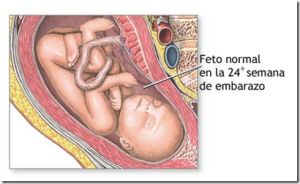

24 semanas de gravidez

24 Semanas de Gestação

- 24 semanas são quantos meses? 24 semanas de gravidez são 6 meses. Com a semana 24 da gravidez, você está na terceira semana do mês 6 da sua gestação.

- Com 24 semanas de gestação, o bebê pesa cerca de 600 gramas! Claro que pode ter uma variação de peso de um bebê para o outro, já que os desenvolvimentos são diferentes.

- As 24 semanas de gravidez referem-se à terceira semana do 6º mês e seu bebê está cada dia maior e mais ativo.

Com 24 semanas de gestação, o bebê pesa cerca de 600 gramas! Tá bom pra você? Pois é, é isso que seu bebê pode pesar agora, um pouco menos, um pouco mais… É relativo, pois há um fator que determina o peso e tamanho da criança, a genética da mamãe e do papai.

Além disso, há também a situação da placenta, e a nutrição que o bebê recebe. Os 30 centímetros mostram o desenvolvimento fetal avançado. Um ultrassom pode mostrar para a mamãe e para o papai um bebê agora mais gordinho e crescido, que gosta de brincar com as mãozinhas e pezinhos.

A velha pergunta: 24 semanas são quantos meses? Com 24 semanas de gravidez, marcamos a chegada da terceira semana do 6º mês, e seu bebê esta cada dia maior e mais ativo. Com isso seus movimentos ficam mais evidentes e muitas das vezes até doloridos. Dores nas costas assim como na parte de baixo do ventre são naturais nesta etapa1. É porque o espaço para o bebê dentro da barriga está cada vez mais limitado e o incômodo começa a se acentuar. As costelas podem ser o brinquedo favorito. E a bexiga então, nem se fala!

Seus olhos que já conseguiam abrir e fechar desde a semana anterior. Agora ganham cílios e a cada dia que passa o bebê ganha mais e mais a aparência do bebê que você irá pegar nos braços em breve. Nesta semana será iniciado o processo de acúmulo de gordura debaixo da pele do bebê. Ele será responsável pelo controle de temperatura após o nascimento. Isso é necessário já que a temperatura fora da barriga é totalmente diferente de dentro do útero2. Acostumado com 36,5 até 37,5 graus do corpo da mãe, ganhará uma resistência maior até que ganhe peso.